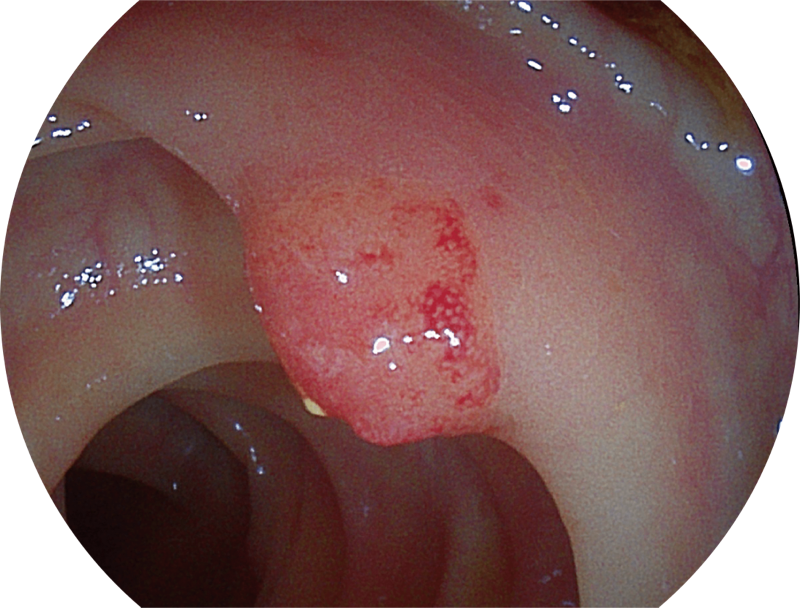

聚谱成像

(Spectral Focused lmaging, SFI)

能够凸显黏膜浅层和中层血管轮廓,适用于中、远景观察下的病灶识别和早癌筛查。

光电复合染色成像

(Versatile Intelligent Staining Technology)

能够凸显黏膜浅层血管轮廓和黏膜表面微结构,适用于中、近景观察下的早癌精确诊断。